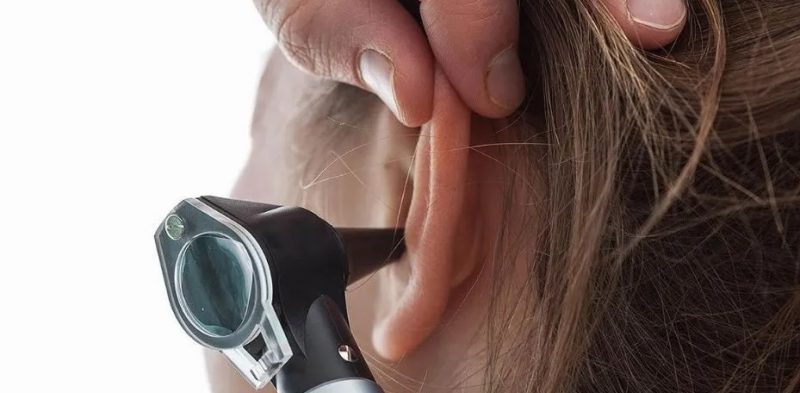

Un hombre de 24 años, identificado como Sr. Lv, ingresó hace unos días en el Hospital Chino de Sanhe, en la provincia de Guangdong, por un fuerte dolor en el canal auditivo.

El Dr. Zhong Yijin, especialista en oído, nariz y garganta de la clínica, contó al AsiaWire, que este individuo argumentó: “Mucho dolor en la oreja, como si algo se estuviera rascando o arrastrando por dentro”.

El médico confirmó las sospechas del hombre después de descubrir una cría recién nacida de cucarachas alemanas, y su madre, en su canal auditivo. “Descubrí más de 10 bebés cucarachas adentro”, afirmó el Dr. Yijiin.

Los médicos pudieron extraer tanto a los bebés como a su madre, uno por uno, del oído de Lv con unas pinzas. Los expertos dicen que las madres de cucaracha alemana (blattella germanica) generalmente contienen de 30 a 40 huevos en su interior.